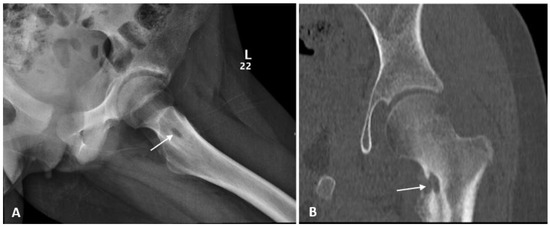

| Index case | 12Y/F | Healthy child | Chronic osteomyelitis | Tissue culture | P. species | VRC total 6 months with surgical debridement | Resolution |